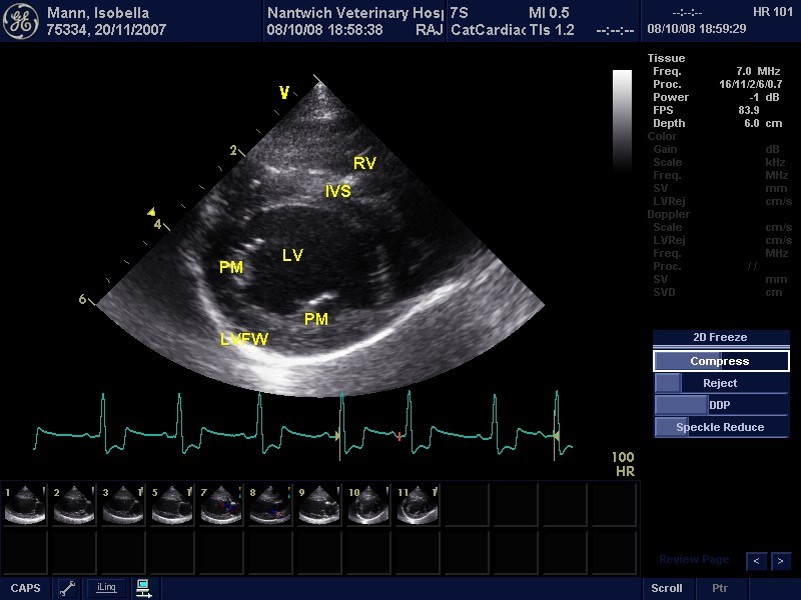

What view is this?

Right parasternal long axis 4 chamber